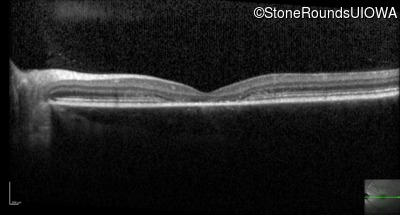

Optical Coherence Tomography - Right - 20/100 -1

Exemplar / OCT Stack

OCT Stack